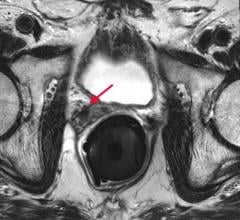

News and new technology innovations concerning how imaging technology can help diagnose and treat prostate cancer can be found on this channel.

June 2, 2016 — Physicians have long used magnetic resonance imaging (MRI) to detect cancer, but a new study describes ...

June 1, 2016 — A new Phase III clinical trial will look to evaluate if magnetic resonance imaging (MRI) can replace the ...